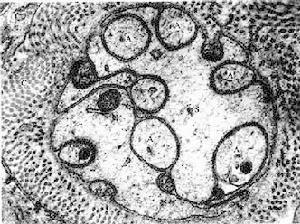

3.視網膜電圖(ERG)檢查 可用於鑑別診斷。